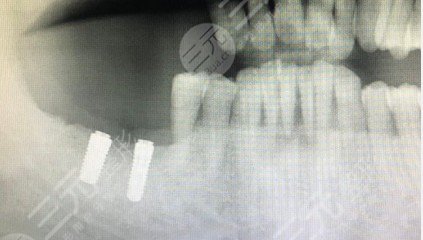

昨日去種植牙了。充分考慮美觀大方,我戴了一顆臨時性活動假牙。當我被下mz劑的情況下,我感覺不上一切痛疼。如今,牙有點兒發(fā)脹,我感覺很難受。過了一會兒,我想去成都恒泰牙科手術(shù)拆線。

拆了線后修復不能說太好,感覺還緩了一陣。由于腫脹少說消失了四天,骨移殖有點兒發(fā)脹,其余是一切正常的。頭孢類抗生素一天三次。昨日早中晚各剛開始吃一次替硝唑,比甲硝唑?qū)ξ干僖稽c刺激,隔三差五就想起吃維生素C。期待快點兒好起來,很愛吃點美味的東西。